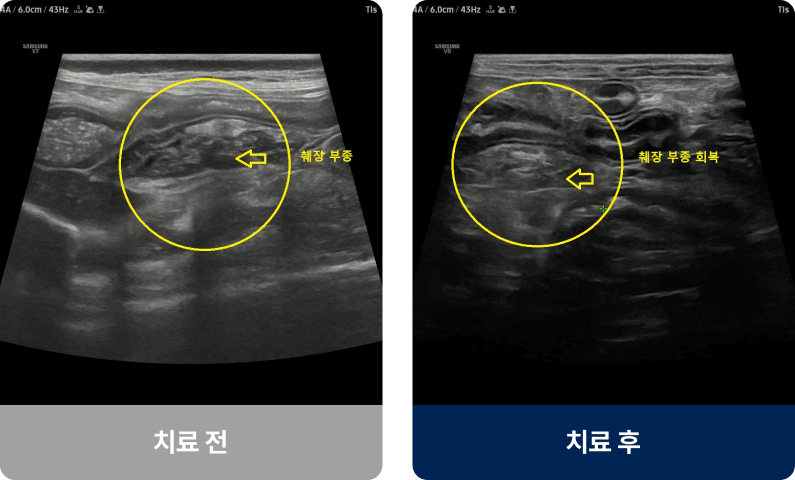

고지방 식이, 과식, 스트레스, 특정 약물 등이 원인이 되어 췌장에 염증이 생기는 질환입니다. 주로 중·노령견이나 비만한 아이에게 많이 발생하며, 밥을 먹은 뒤 구토하거나 복통으로 웅크리는 증상을 보입니다. 진행되면 식욕 저하, 체중 감소, 무기력, 탈수로 이어질 수 있습니다.